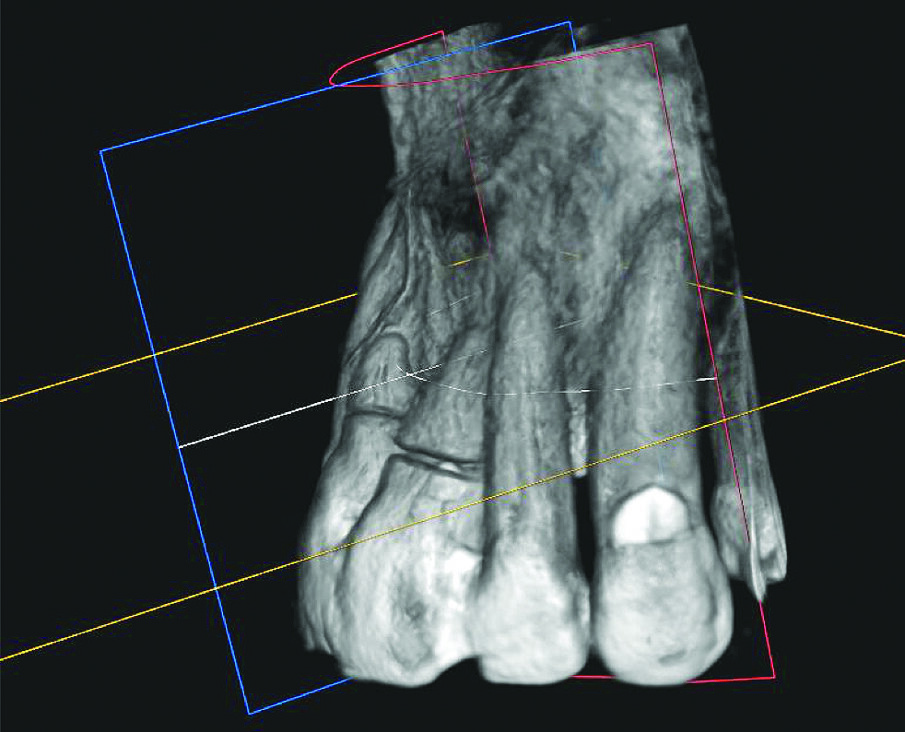

Budući da se to nije moglo isključiti za zub 21, u narednim posjetima provedeno je endodontsko liječenje s naknadnim punjenjem korijenskog kanala s MTA-om do pukotine (Slika 3.). Budući da je pacijent izrazio želju da se ne narušava estetika, za splintiranje je upotrijebljena palatinalna udlaga od PMMA-e (Slika 4.). Nakon tri mjeseca uočena je sve veća promjena boje zuba 21 i perzistentna pomičnost II. stupnja (Slika 5.). Nakon detaljnog informiranja o raznim mogućnostima liječenja kliničar i pacijent donijeli su odluku o implantoprotetskoj terapiji. CBCT snimljen tijekom planiranja terapije (Slika 6.), pokazao je blizak odnos prema vestibularnoj koštanoj lameli (položaj korijena I. razreda)14. Da bi se stvorio stabilan profil mekog i tvrdog tkiva i pacijentu što prije osigurao dobar estetski rezultat, kliničar se odlučio na imedijatnu implantaciju uz primjenu socket shield tehnike.

Slika 6. CBCT prije implantacije: vrlo tanka bukalna koštana lamela i bliski odnos korijena s korteksom